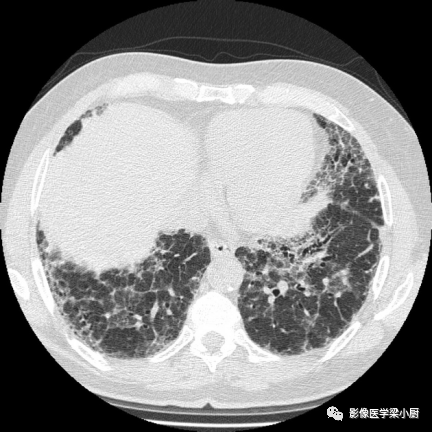

2.网格:网格影一般分布于两肺基底部、胸膜下,常伴结构扭曲。网格影不等同于小叶间隔增厚。

双肺底弥漫性网格状改变